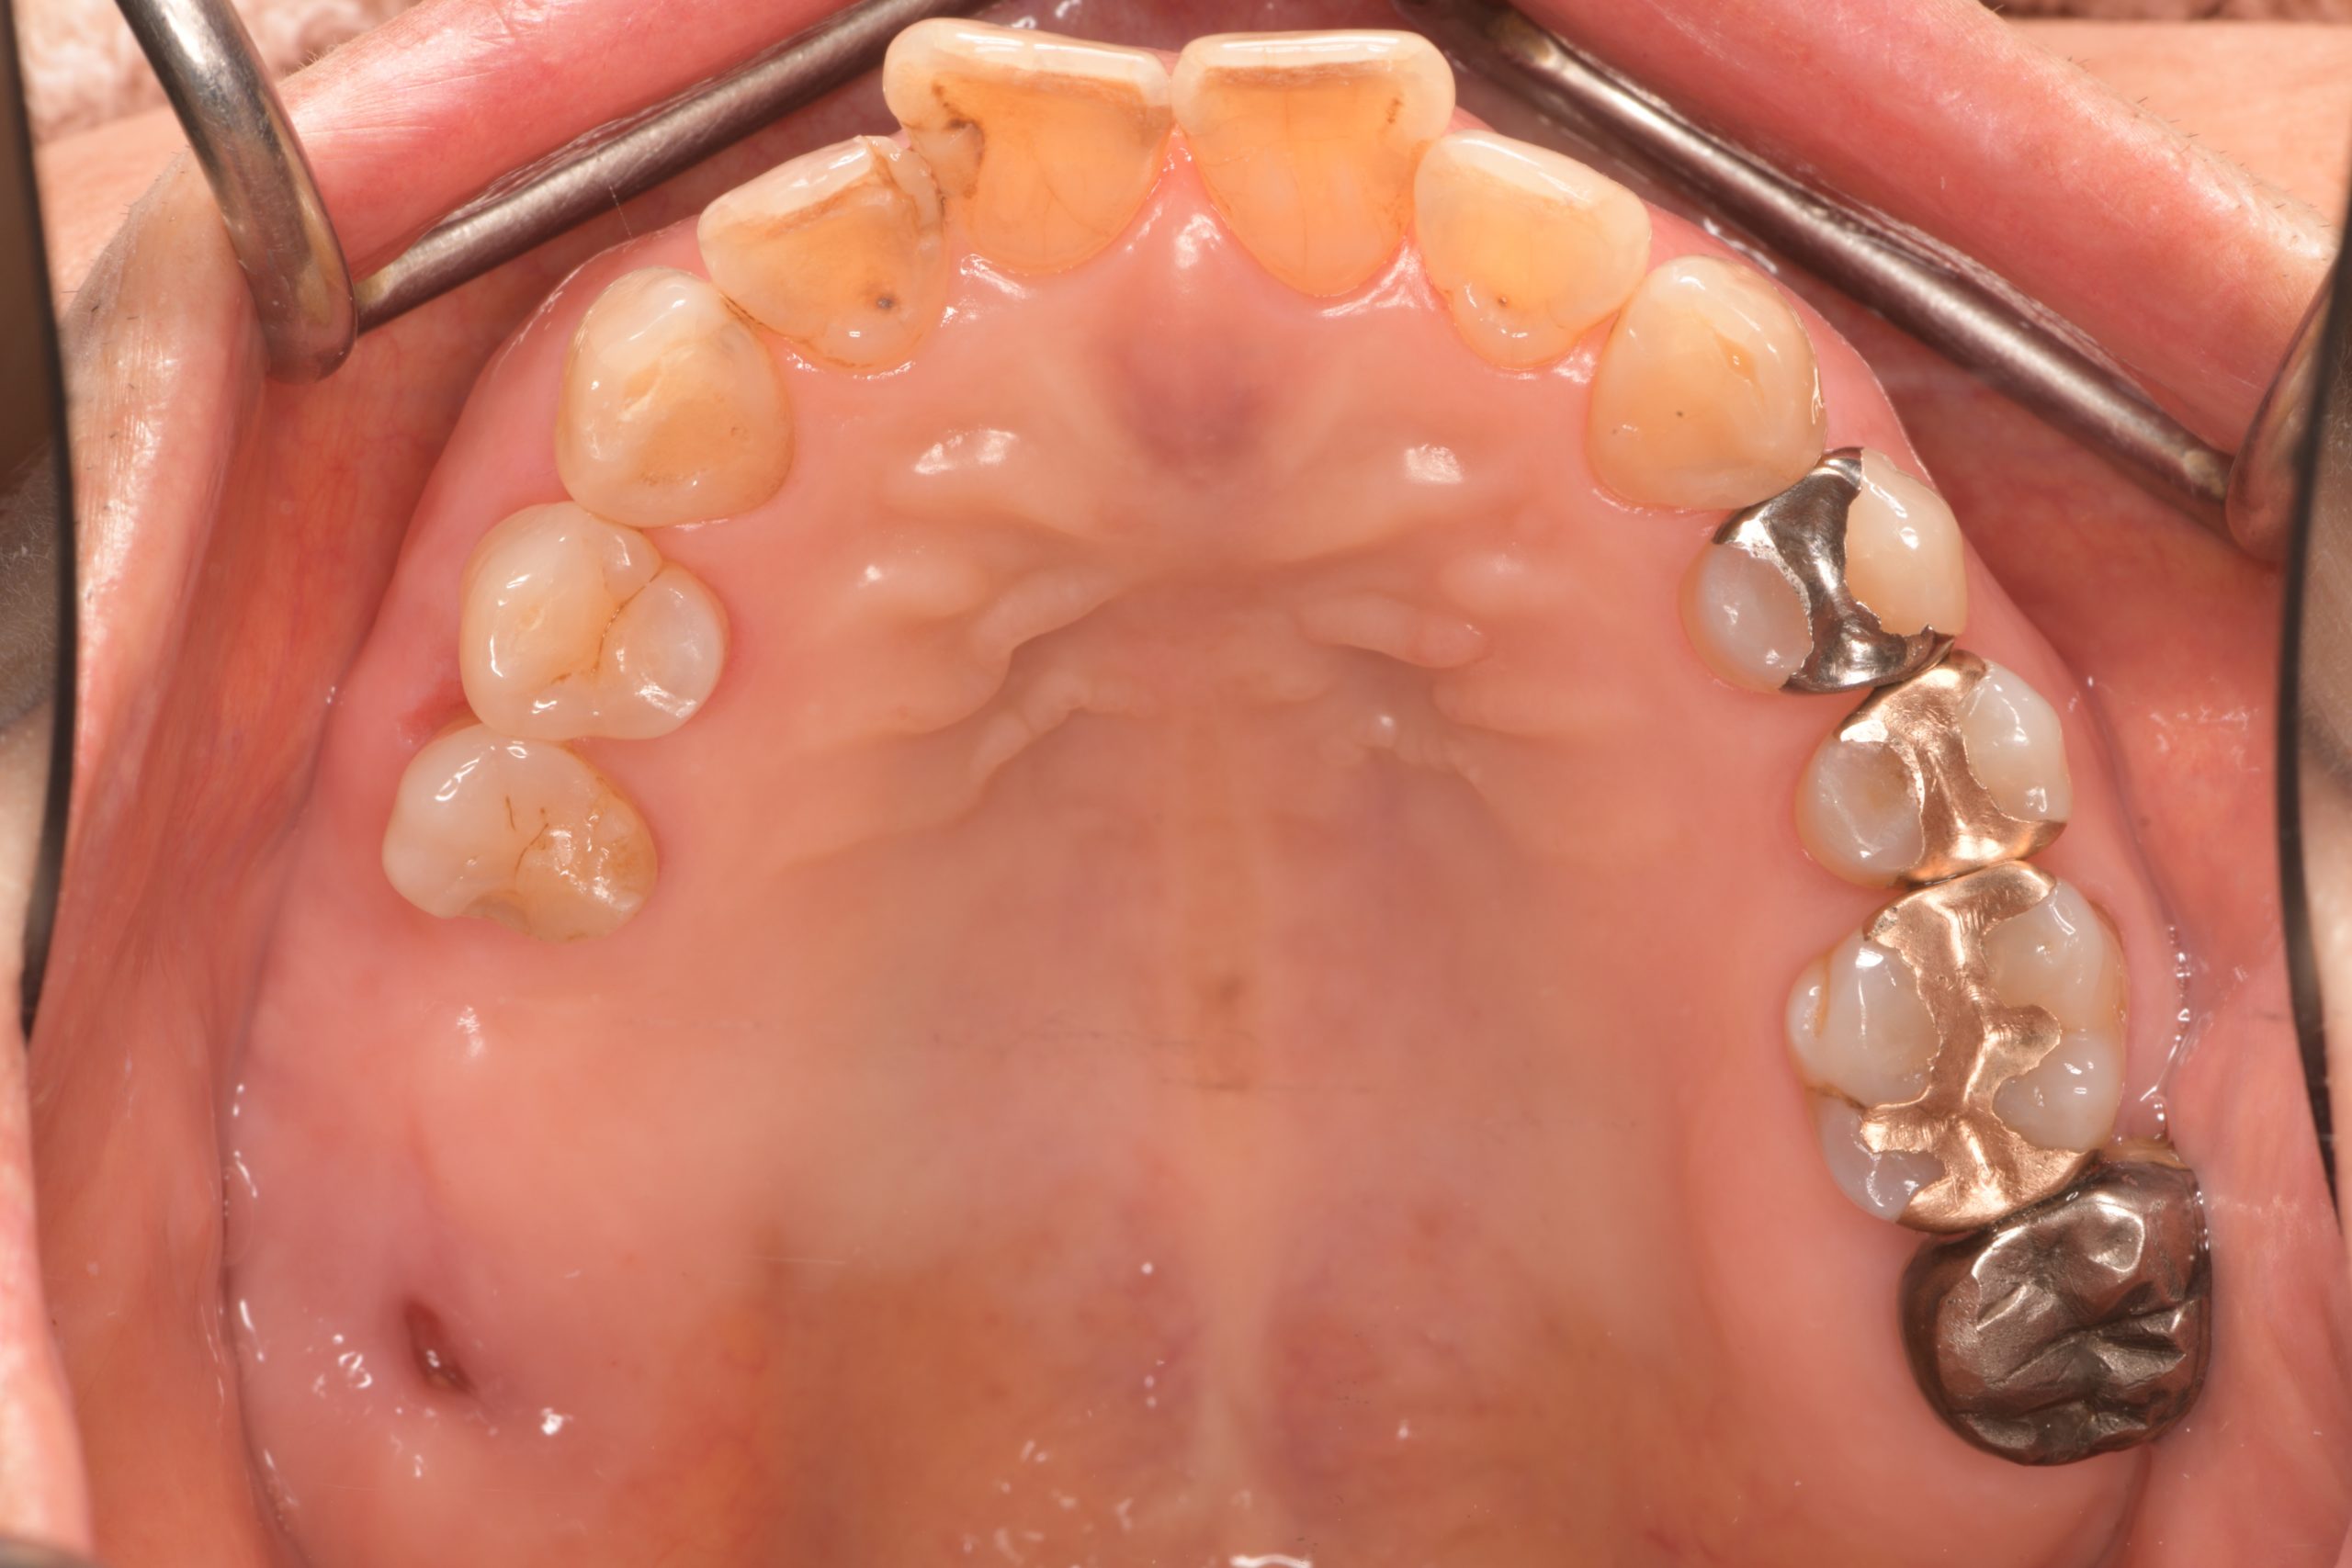

左下臼歯部インプラント治療前

左下臼歯部インプラント上部構造装着前

左下臼歯部インプラント治療完了